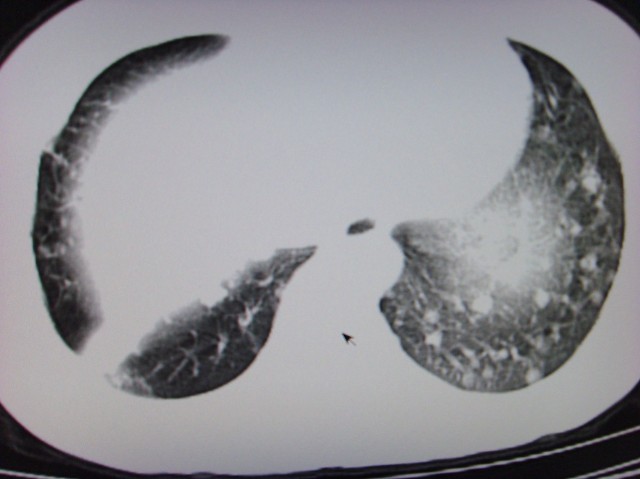

标题: CT7125:中央性肺Ca.

典型 中央型ca伴双肺、淋巴结转移

右下中心型肺癌伴双肺转移、纵隔淋巴结转移,癌性淋巴管炎可能性大

典型--右下中心型肺癌伴双肺转移、纵隔淋巴结转移,癌性淋巴管炎可能性大

中心型肺癌伴双肺转移及纵隔淋巴结转移,癌性淋巴管炎

典型的中央型ca,肿快和肺门分界不清,肿快边界模糊,呈毛刺状。伴淋巴结转移。